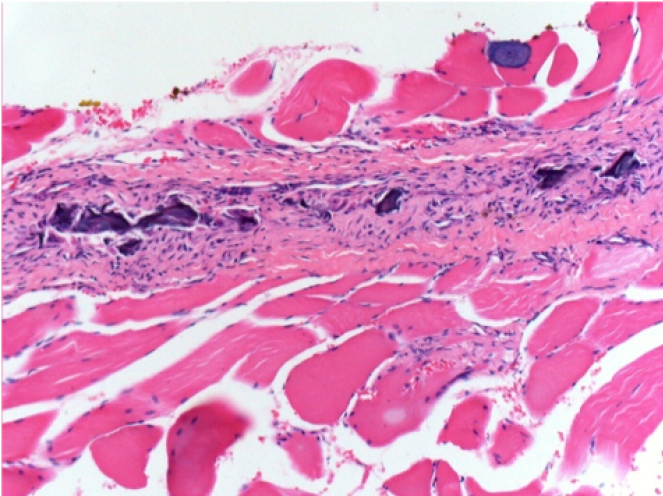

Endopeel Injection in Subcutaneous Tissue

0.5 ml ( 5x 0.1ml) Endopeel SC Injection in the right subcutaneous pretibial area.

L:200x-Control-SC

R-D10-SC-200X

R-D30-SC-200X

R-D90-SC-200X

R-D210-SC-200X

R-D210-SC-400X

- Endopeel induces a selective reversible myofibrolysis and inflammatory reaction on a period of 1 month, approximately

-

- Muscular changes are reversible in almost full totality

- The muscle is the better place to inject Endopeel because of more efficacity, control and duration of its action

- No necrosis nor abcess have been found all over the study.